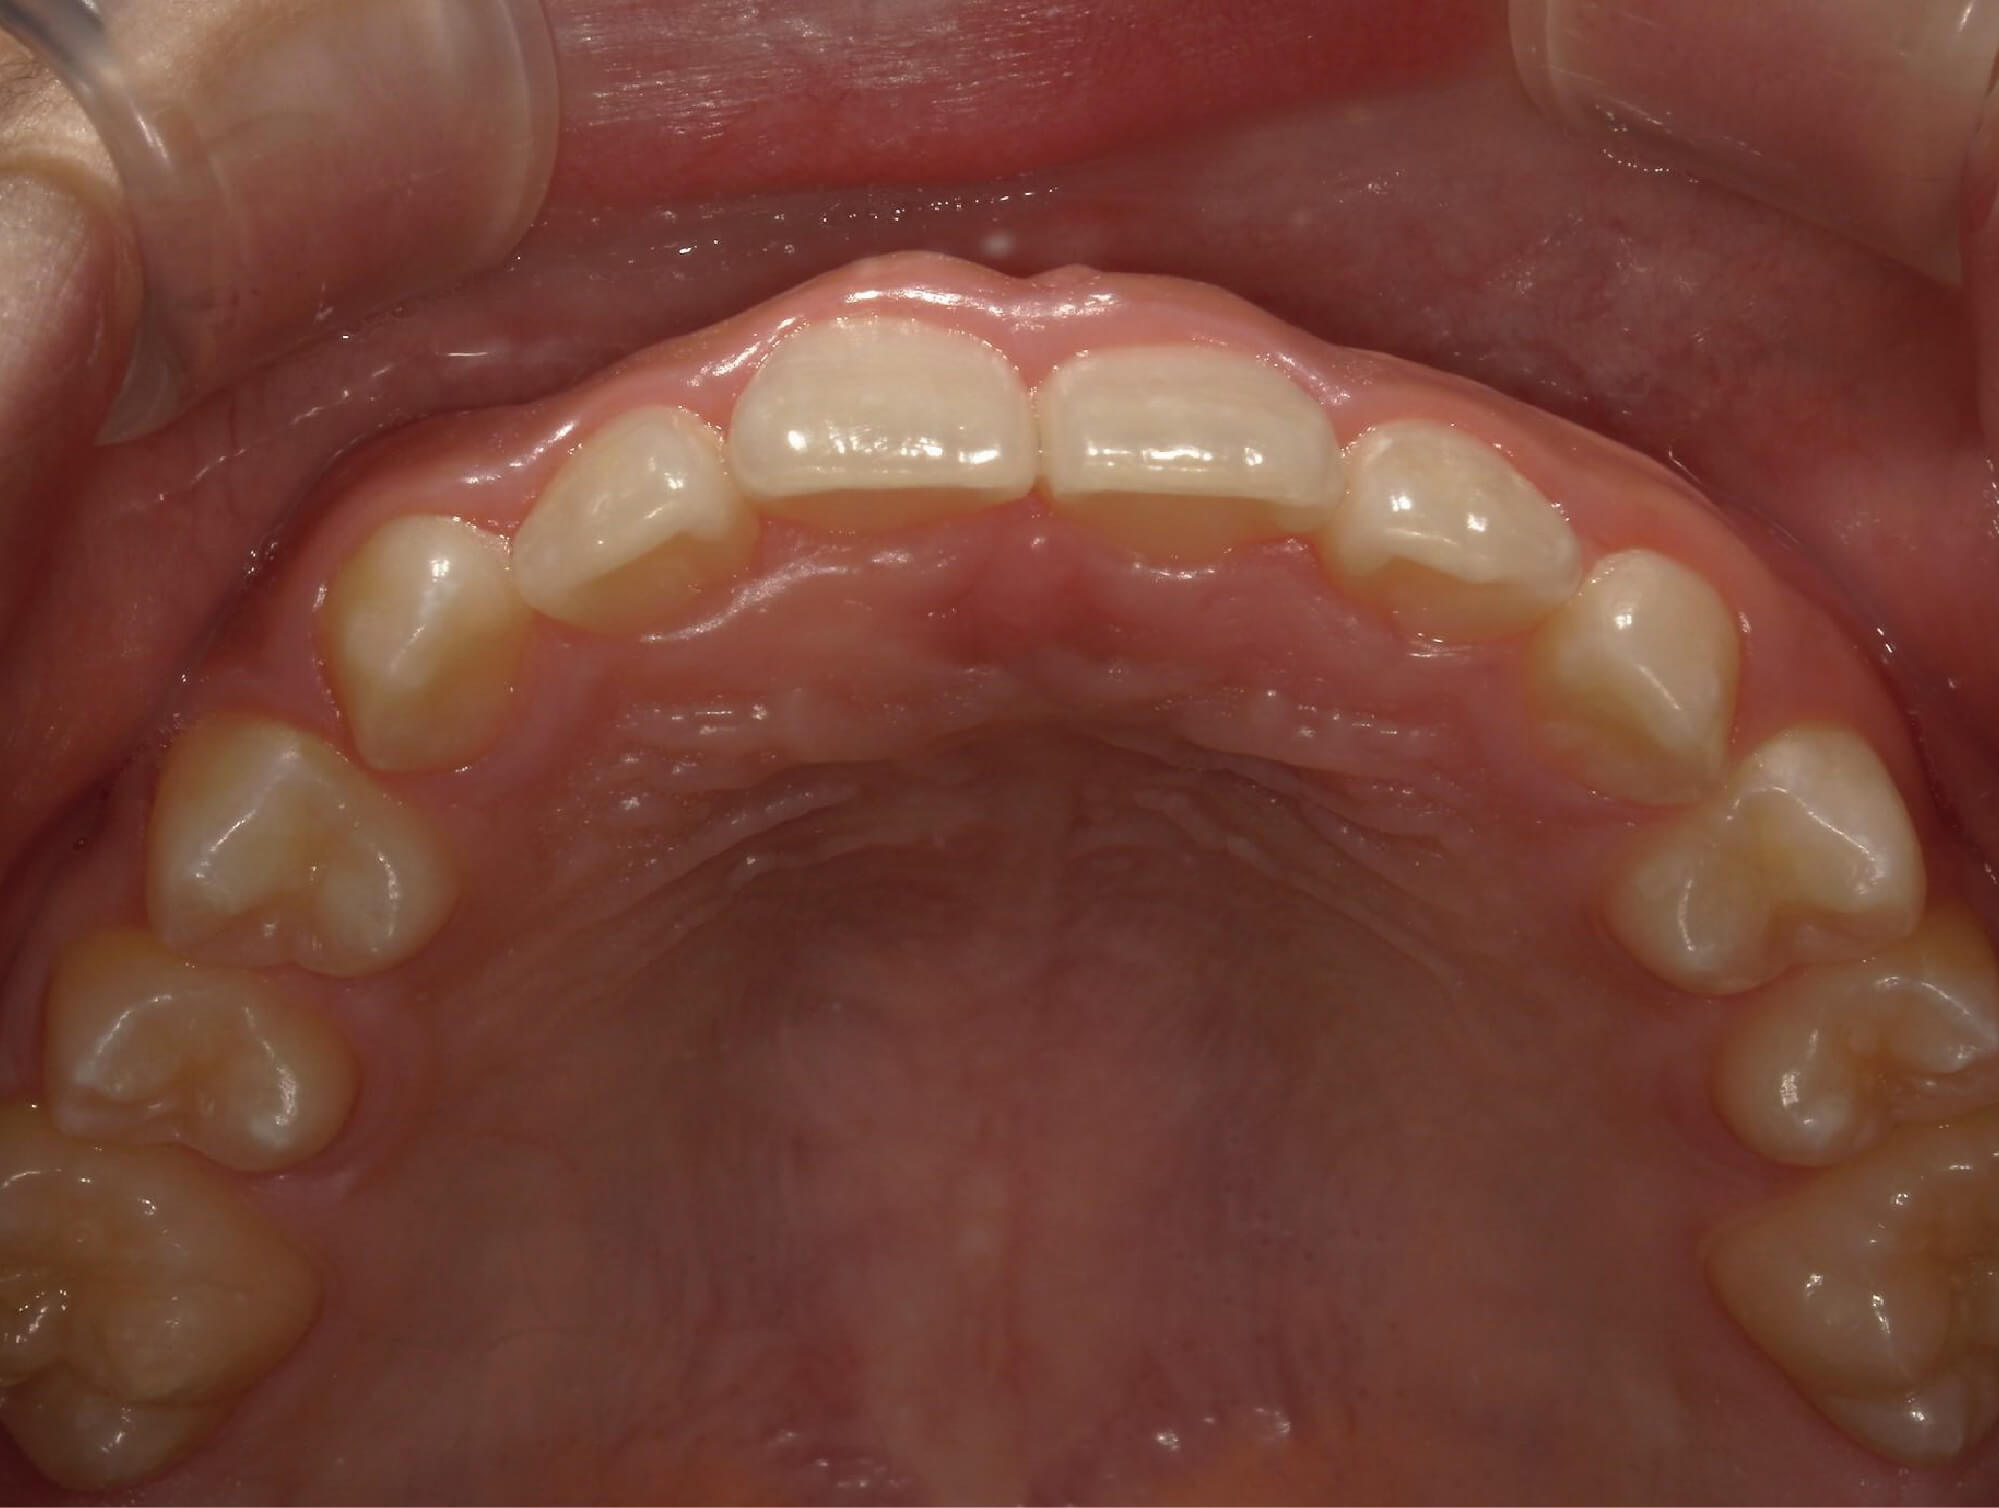

| 年齢・性別 | 8歳9ヶ月の女児 |

|---|---|

| 主訴 | 歯並びの乱れを気にされて来院された患者様です。将来的なスペース不足と歯のねじれ(翼状捻転)が懸念されました。 |

| 治療期間・回数 | 2年10ヶ月・19回 |

| 費用 | 430,000円(税別) |